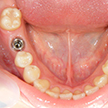

12. インプラント歯冠作製前

インプラント体埋入から約3ヶ月後です。しっかりインテグレーション(骨との結合)が得られたので、これから上部構造を作製します。この場合は既成のアバットメントを装着しました。インプラント周囲歯肉も予想以上に健全です。